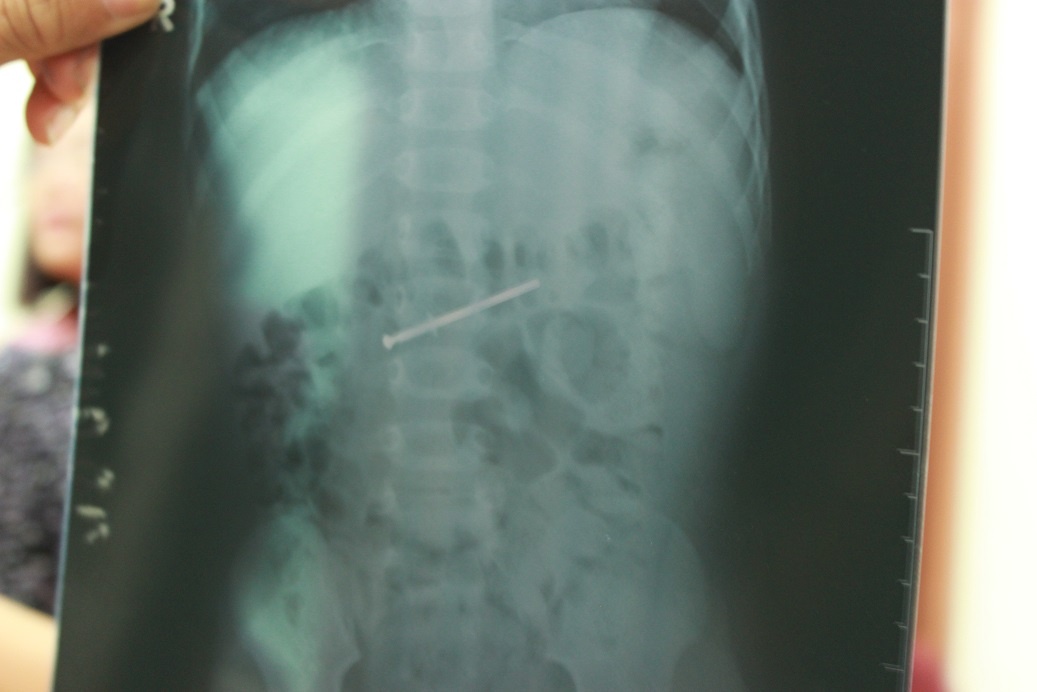

"Sau khi chụp phim X-quang, chúng tôi phát hiện dị vật trong ruột non của bé và tiến hành nội soi. Cây đinh di chuyển nên đã làm tổn thương và trầy xước dạ dày của bé. Rất may mọi chuyện chưa diễn tiến quá phức tạp", bác sĩ Dũng cho biết.

| Cây đinh qua phim chụp X - Quang. |